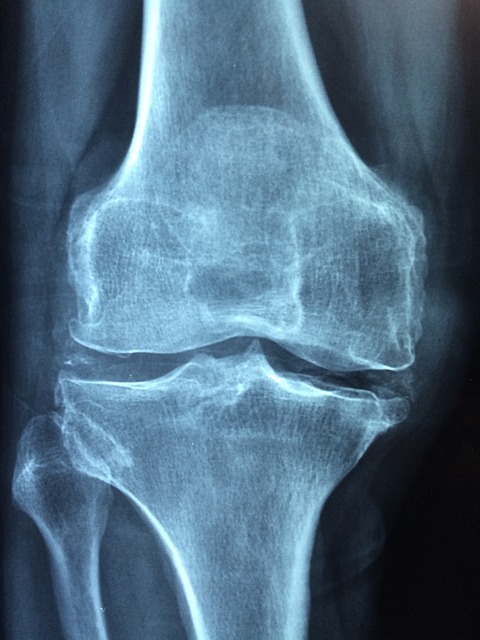

골다공증은 뼈의 밀도가 감소하고 뼈의 강도가 약해지는 질환으로, 뼈가 부러지기 쉬운 상태를 말합니다. 이 질환은 보통 뼈의 노화와 관련이 있으며, 나이가 들수록 발생 위험이 증가합니다. 골다공증은 주로 고령층에서 흔히 발생하지만, 잘못된 생활 습관이나 유전적인 요인 등으로 인해 젊은 층에서도 나타날 수 있습니다.

골다공증이 생기면 뼈의 미세구조가 손상되고, 뼈의 강도가 약해져 작은 충격에도 골절 위험이 높아집니다. 특히 척추, 고관절, 손목 부위에서 골절이 자주 발생하며, 이러한 골절은 심각한 통증과 함께 일상생활에 큰 지장을 줄 수 있습니다.